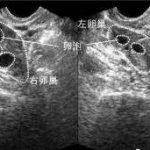

试管婴儿是目前临床上治疗不孕的一种技术手段。主要是指精子和卵子在体外受精培养3~5日,再移回到宫腔内。具体费用与当地消费水平有直接关系,每个地区都存在物价差。费用大约在3万元到5万元不等。因为试管婴儿前期需要一些相关的治疗,试管并不是一次性能成功,需要二次三次的可能。所以具体费用要与临床实际情况有直接关系。